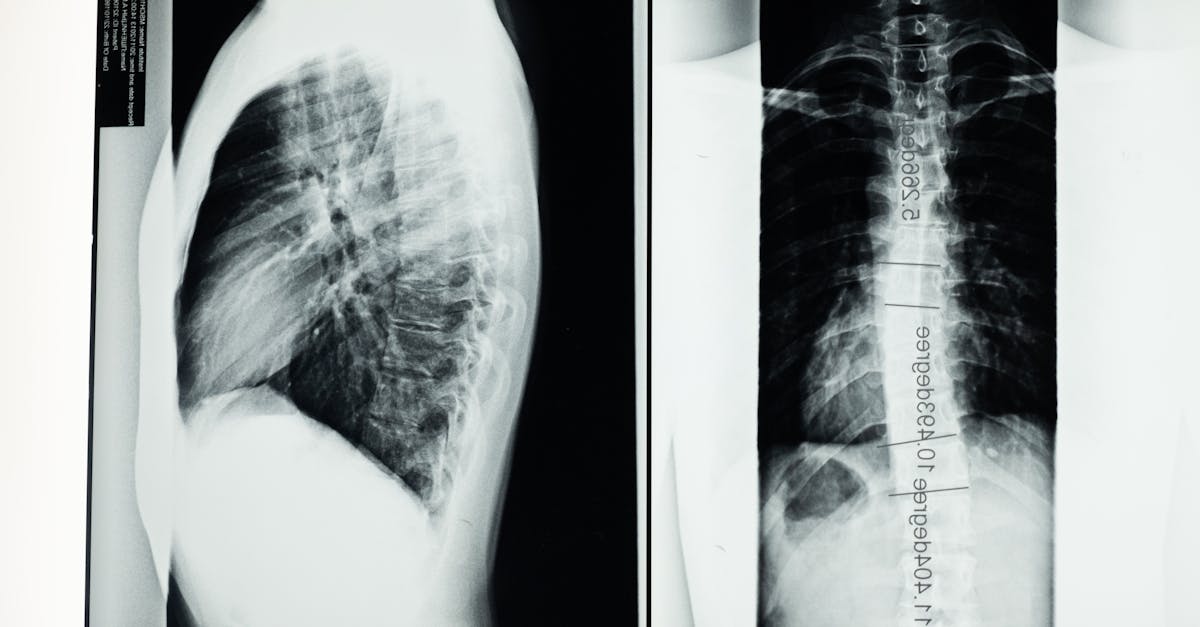

Capacitando a los pacientes con conocimientos sobre la postura. Descubra los fundamentos de la escoliosis, una curvatura de la columna vertebral que afecta a millones de personas. Aprenda sobre sus causas, síntomas, opciones de tratamiento y cómo manejar esta afección eficazmente para una vida más saludable.Vivir con escoliosis presenta desafíos únicos, especialmente en lo que respecta a la mejora de la postura y el bienestar físico general. Este artículo explora el potencial del enfoque holístico de Pulse Align para ofrecer apoyo complementario de alineación mediante técnicas destinadas a mejorar la salud neuromuscular. y promover la simetría corporal. Al centrarse en diversos métodos, como ejercicios de postura, yoga para la postura y entrenamiento del core, Pulse Align ayuda a las personas a recuperar su salud y lograr un equilibrio natural. Entendiendo la escoliosis y su impacto

La escoliosis se caracteriza por una curvatura anormal de la columna vertebral, que puede provocar diversos problemas secundarios, como una postura de cabeza adelantada, hombros encorvados e inclinación pélvica anterior. Estos problemas posturales pueden agravar el malestar, afectando las actividades diarias y la calidad de vida en general. Reconocer la necesidad de estrategias de manejo efectivas es crucial para quienes padecen esta afección.